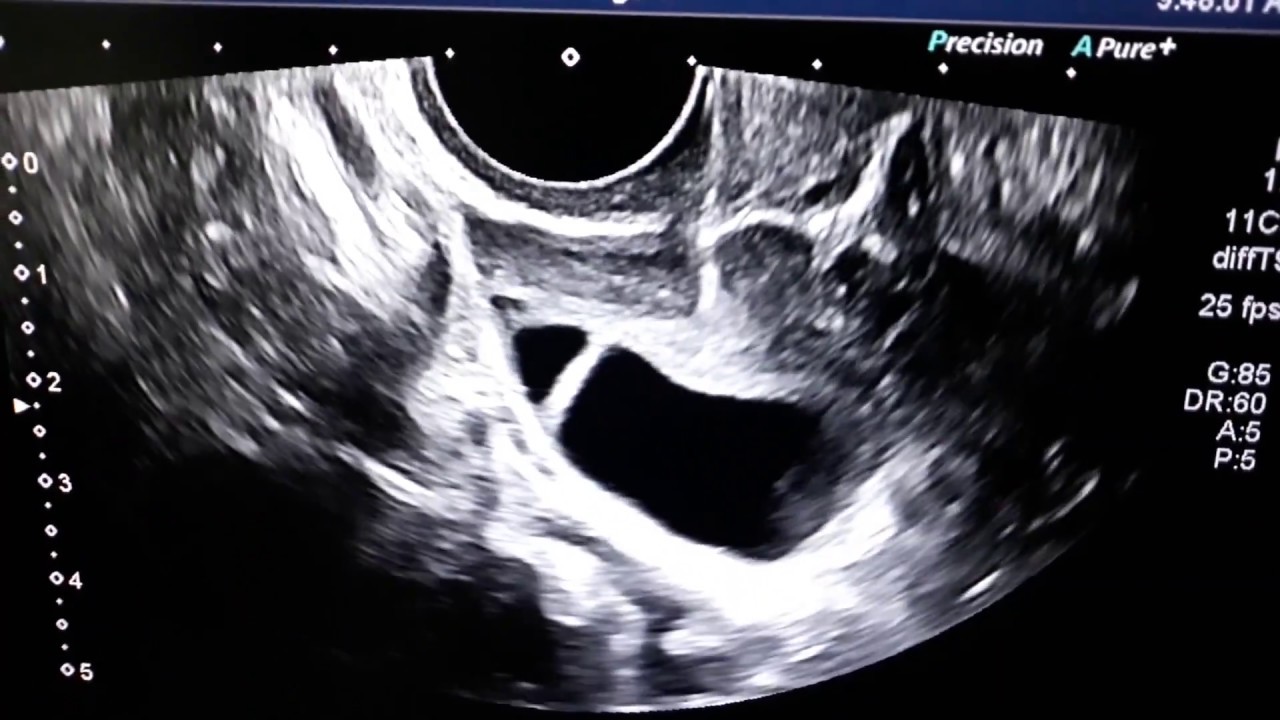

IVF Egg or Ovum Retrieval / Collection Procedure in IVF by Dr Arun

Описание: How are the eggs collected (retrieved) during an IVF Cycle ?

Using an vaginal ultrasound, needle is passed and the follicular fluid is aspirated.

This video shows how the follicular fluid is aspirated during an IVF Egg retrieval procedure of ICSI Cycle. This procedure is also called IVF Egg pickup or oocyte retrieval